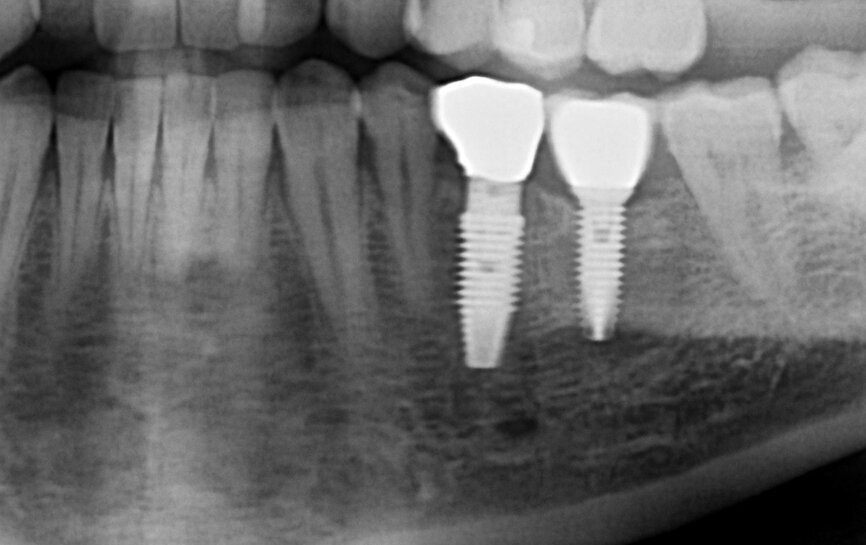

Fig. 9: Radiographic evaluation of the final crown.

At the one-year follow-up visit, the soft-tissue contours adjacent to the implant restoration and the buccal bone volume and convexity still resembled those adjacent to the natural teeth. Bone levels around the implant appeared stable during radiographic evaluation (Fig. 9). No perceptible loss occurred. The artificial crown had an emergence profile mimetic of that of a natural tooth. At the two-year follow-up visit, the tissue contours looked stable and appeared even to have improved when compared with the one-year follow-up visit (Fig. 10).